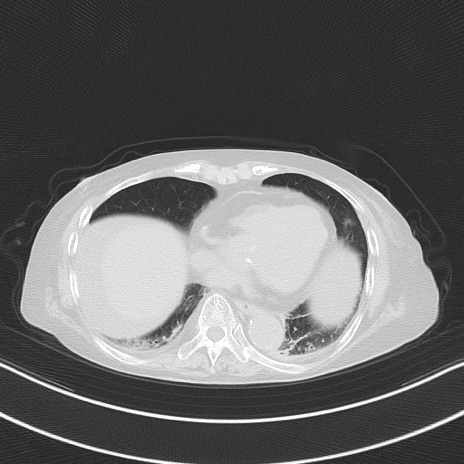

症例40(横断像)他院1日前

横断像

他院CT